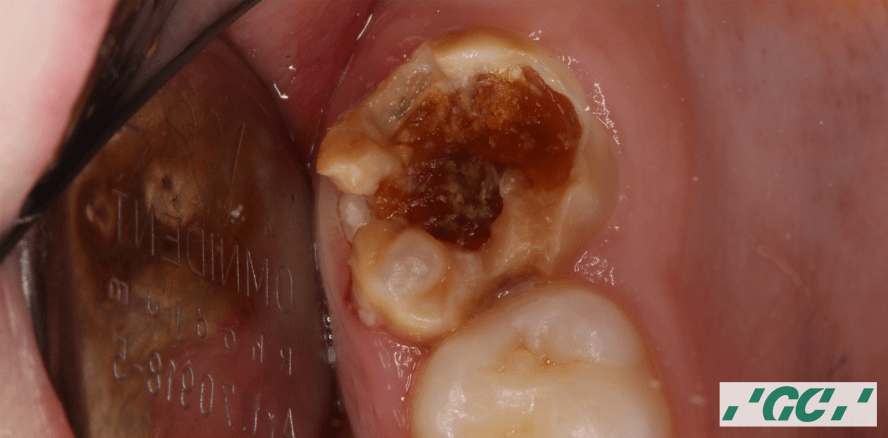

Eine aktuelle Studie zeigt, dass 2019 in Deutschland rund 230.000 der 6- bis 9-Jährigen aufgrund von MIH behandelt wurden. Unterstützung für Zahnärzte und Eltern mit betroffenen Kindern bietet das MIH-Kit von GC.